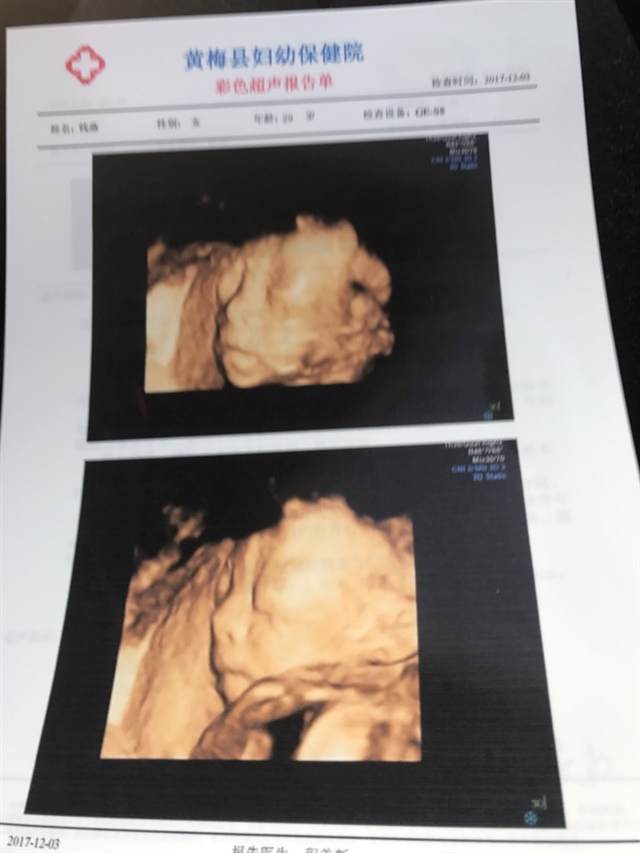

宝宝4个月7天

胎儿双肾盂未见明显分离,女孩几率大一些。

孕24周+5天

目测女宝的可能性大一些哦

男孩,单子写的很清楚